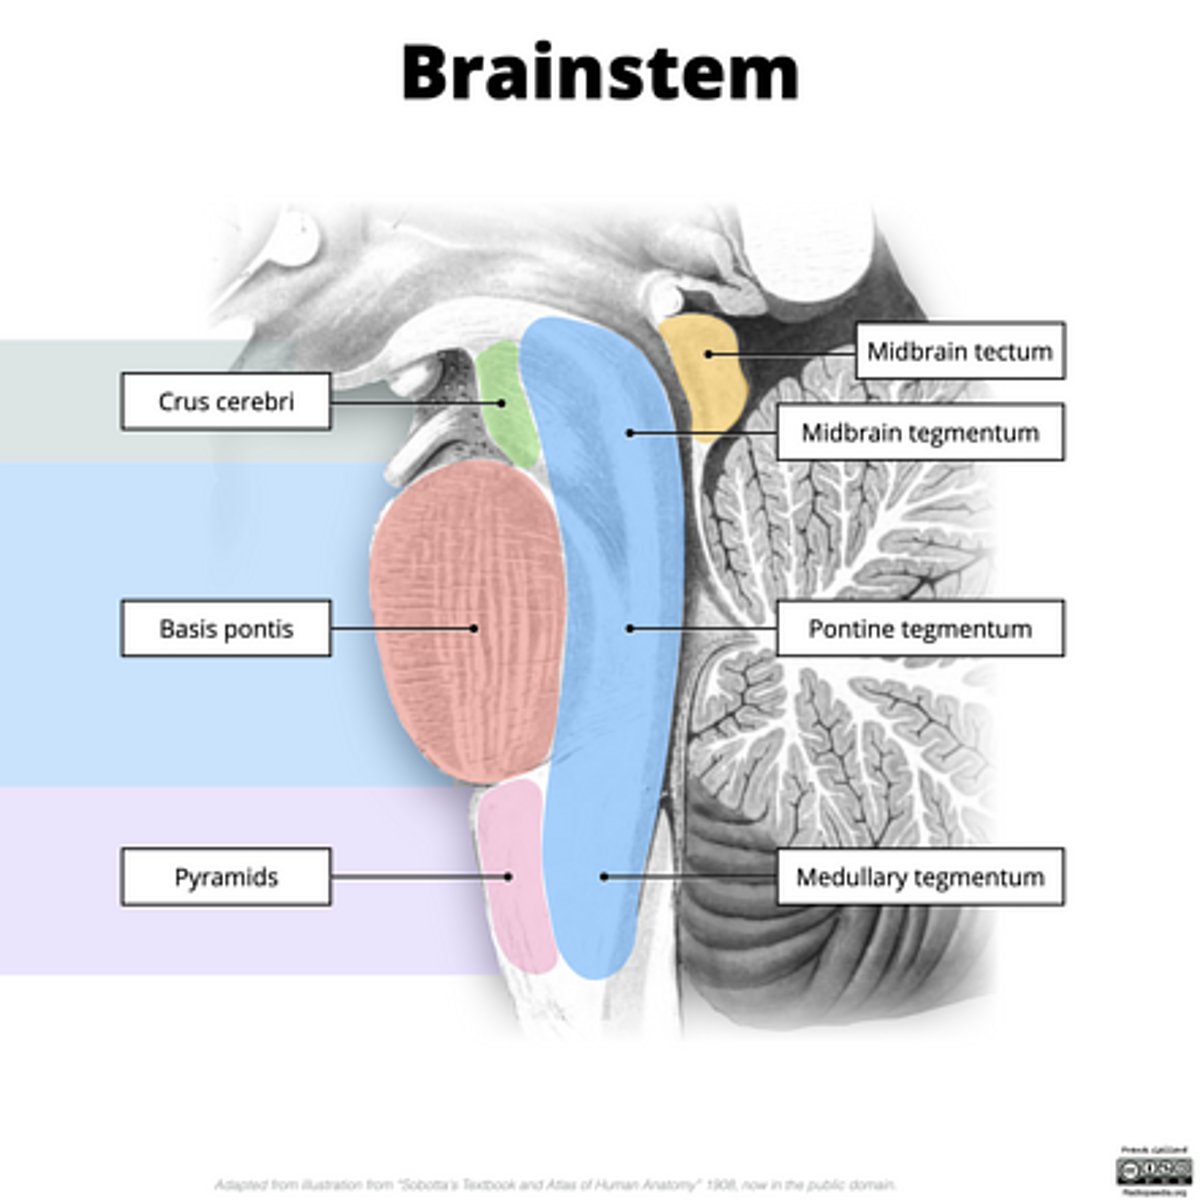

What are the structures of the brainstem?

1. mesencephalon (midbrain)

2. pons

3. medulla oblongata

What is the tectum?

roof of the midbrain

What is the tegmentum?

floor of midbrain

What are the fibers of the tegmentum?

ascending fibers

What is the crus cerebri?

part of the cerebral peduncles which contain descending tracts

What are the fibers of the crus cerebri?

descending fibers

image -- 5